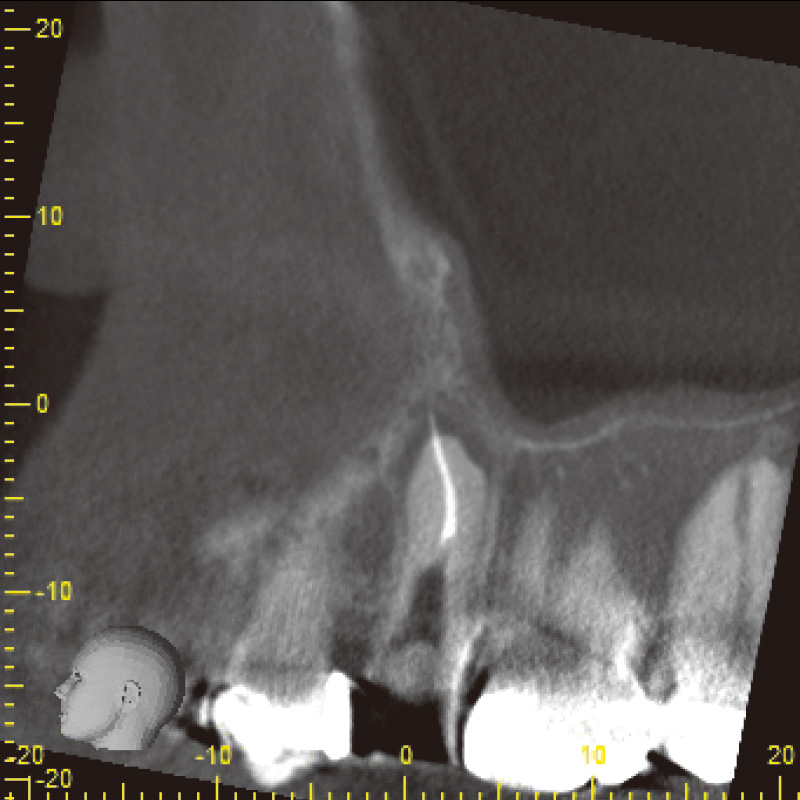

患者は35歳男性で主訴は咬合痛であった。自発痛(-)咬合痛(+)・打診痛(+)・根尖部腫脹(中等度)根尖圧痛(軽度)であり、デンタル及びCBCTでは根尖部透過像・著明な外部吸収及び根尖孔破壊・根管充填材・太いポストコア及び根管壁の菲薄化を認めた(症例1-1, 1-2)。

症例1-1 初診時デンタルX線画像![[写真] 初診時CBCT画像](/academic/dentalmagazine/wp-content/uploads/sites/2/2025/11/195-6_photo02.jpg)

症例1-2 初診時CBCT画像( Veraviewepocs 3Dfにて撮影)![[写真] 多量の排膿](/academic/dentalmagazine/wp-content/uploads/sites/2/2025/11/195-6_photo03.jpg)

1-6 根管充填後6か月のCBCT画像

6か月間の経過観察を経て、CBCTにて根尖部透過像の著明な縮小を認め、最終補綴へ移行した(症例1-6)。